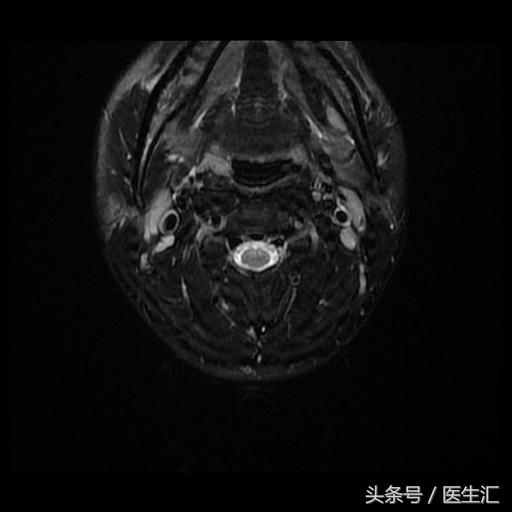

颈MRI:长节段髓内病变(前角)(见图13、14、15、16)

头颅MRI:(见图17)

专家判读:小脑中脚、苍白球、白质、胼胝体皆有病变。